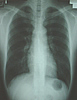

| ・ |

肺に異常な影があるか、心臓の形や大きさに異常があるかを調べます。 |

肺結核、肺炎、肺癌、肺膿傷、肺気腫、気管支拡張症、心臓肥大などの病変の発見もできます。 |